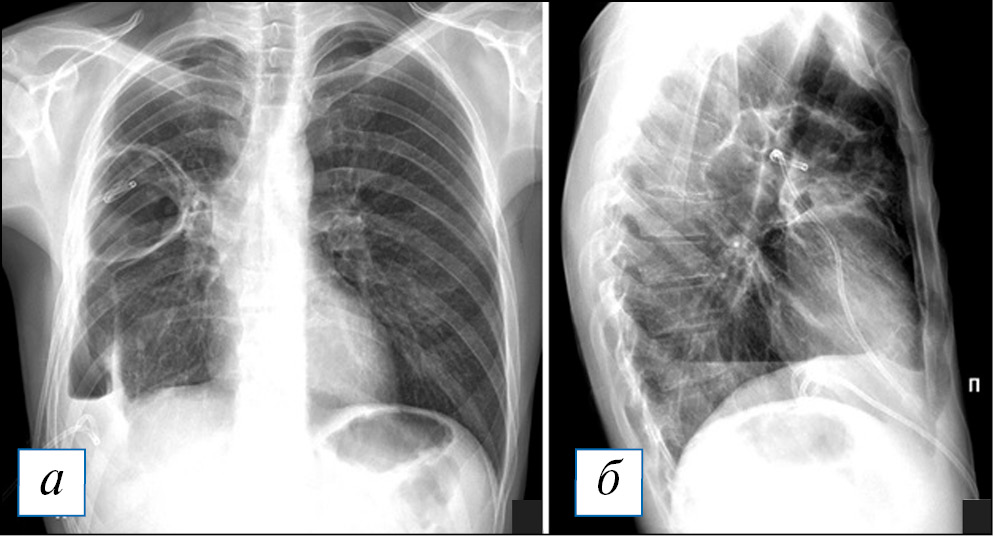

Диагностика острого абсцесса легкого по данным рентгенографии после его частичного опорожнения не представляет сложности: это кольцевидная тень с уровнем жидкости, контуры «кольца», обычно достаточно четкие (рис. 6). При рентгеноскопии или повороте тела можно наблюдать и изменение уровня жидкости в абсцессе (рис. 7). Сложнее с диагностикой абсцесса при его формировании, когда затенение не имеет типичных черт и может быть неправильной формы: оно представлено чаще круглой тенью или отграниченным затенением, центральные отделы которого могут быть несколько неоднородными, однако этот признак очень непостоянный.

Рис. 6. Рентгенография органов грудной клетки в прямой и правой боковой проекциях. Острый абсцесс в верхней доле правого легкого. В верхней доле справа имеется кольцевидная тень с небольшим горизонтальным уровнем жидкости, что свидетельствует о почти полном дренаже абсцесса. В S3 рядом с полостью — неоднородное затенение и сгущение легочного рисунка. [Изображения из архива авторов]. / Fig. 6. Chest X-ray. Acute abscess in the upper lobe of the right lung. In the upper lobe on the right there is a ring-shaped shadow with a small horizontal level of fluid, which indicates almost complete drainage of the abscess. In S3, next to the cavity, there is a non — uniform shading and thickening of the pulmonary pattern. [Images from the authors’ archive].

Рис. 7. Рентгенография органов грудной клетки в прямой и правой боковой проекциях. Острый абсцесс в верхней доле правого легкого. Полость в верхней доле справа на 1/3 заполнена жидкостью с горизонтальным уровнем, который соответствует положению пациента во время снимка (стрелки). [Изображения из архива авторов]. / Fig. 7. Chest X-ray. Acute abscess in the upper lobe of the right lung. The cavity in the upper lobe on the right is filled with liquid by 1/3 with a horizontal level that corresponds to the position of the patient during the image acquisition (arrows). [Images from the authors’ archive].